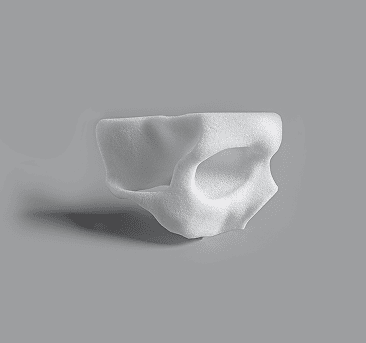

Complete Orbit